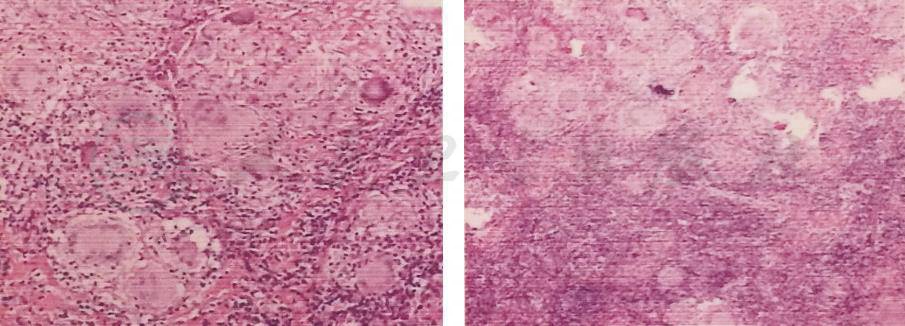

1.左锁骨上淋巴结活检病理 肉芽肿形成,倾向结核(图2)。

图2 左锁骨上淋巴结活检病理

2.支气管镜+右下肺支气管镜下肺活检 镜检诊断为支气管炎,右下叶背支病检为肉芽肿性炎,考虑结核(图3)。

图3 支气管镜下肺活检病理

3.CT引导下经皮肺穿刺活检(图4) 右下肺肉芽肿性炎,未见干酪样坏死,结核不能排除。特殊染色结果:PAS(-),消化 PAS(-),抗酸染色(-)。

图4 经皮肺穿刺活检病理